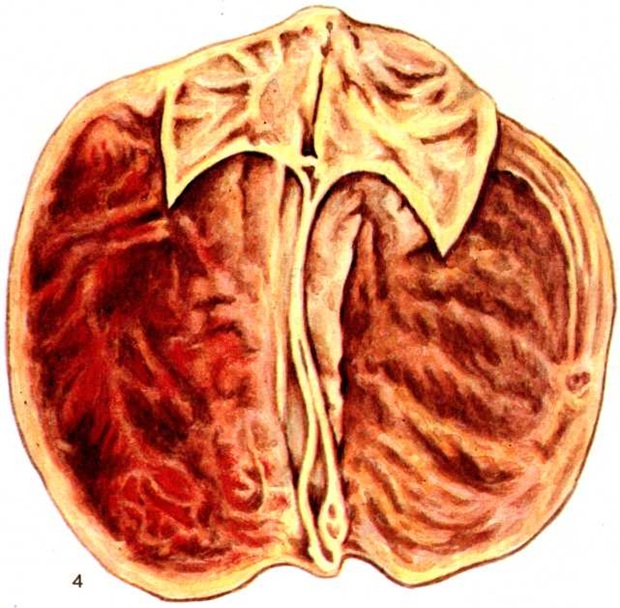

ПахименингитПахименингит (pachymeningitis; греческий pachys толстый, плотный + meninx, meningos оболочка + -itis) — воспаление твёрдой оболочки головного и спинного мозга. Воспалительный процесс твёрдой оболочки головного мозга называют церебральным пахименингитом, а твёрдой оболочки спинного мозга — спинальным пахименингитом. В зависимости от того, какие слои оболочки поражены, различают наружный, внутренний и внутри-оболочечный Пахименингит По характеру воспалительного процесса различают серозный, геморрагический и гнойный Пахименингит, по течению — острый и хронический Пахименингит Патологоанатомические изменения при серозном Пахименингит характеризуются разрыхлением, отёком и резким полнокровием твёрдой оболочки головного и спинного мозга. При геморрагическом внутреннем Пахименингит в патологический процесс вовлекается твёрдая оболочка головного мозга, чаще верхнелатеральной поверхности лобной и височной долей полушария головного мозга, иногда обоих полушарий мозжечка, реже области турецкого седла. В твёрдой оболочке спинного мозга геморрагический внутренний Пахименингит встречается крайне редко. При этой форме происходит геморрагическое пропитывание или расслоение твёрдой оболочки головного мозга вследствие разрыва стенок или флебита мозговых вен в зоне впадения их в синусы твёрдой мозговой оболочки. Макроскопически поражённая оболочка имеет пёстрый вид за счёт чередования буровато-коричневых старых очагов и скопления крови в образующихся в результате повторных кровоизлияний полостях (цветной рисунок 4). В дальнейшем содержимое полостей полностью обесцвечивается и образуются так называемый гигромы твёрдой оболочки головного мозга. Микроскопически при геморрагическом Пахименингит обнаруживаются очаги кровоизлияний разной давности и полости, внутренняя поверхность которых выстлана эндотелием (рисунок 1). Организация геморрагических масс (смотри полный свод знаний: Организация в патологии) происходит путём врастания в них грануляционной ткани с образованием тонкостенных сосудов (рисунок 2). В грануляционной ткани выявляются скопления гемолизированной крови и отложения гемосидерина; в формирующейся фиброзной капсуле отмечается пролиферация макрофагов (рисунок 3). Капсула может быть инфильтрирована лимфоидными и плазматическими клетками. Особенностью геморрагического Пахименингит является медленное развитие процессов организации и недостаточно выраженное свёртывание излившейся крови вследствие малого содержания в ней фибрина или примеси цереброспинальной жидкости. В центральных отделах полостей процессы организации могут развиваться быстрее, что сопровождается в ряде случаев отложением солей кальция или окостенением твёрдой оболочки головного мозга. При гнойном Пахименингит твёрдая оболочка головного и спинного мозга полнокровна, гнойный или фибринозно-гнойный экссудат располагается на наружной поверхности оболочки или в субдуральном пространстве, постепенно подвергаясь организации и отграничению спайками; при этом образуются экстра или субдуральные абсцессы. Микроскопически в твёрдой оболочке головного и спинного мозга обнаруживаются периваскулярные инфильтраты из сегментоядерных лейкоцитов и грануляционная ткань разной степени зрелости. При стихании процесса развивается фиброз оболочки. При хронический Пахименингит развивается фиброз твёрдой оболочки головного и спинного мозга и происходит сращение её с окружающими тканями. Распространение процесса по протяжению твёрдой оболочки спинного мозга способствует образованию муфтообразного утолщения с последующим сдавлением корешков спинномозговых нервов и их атрофией. При туберкулёзе, сифилисе, актиномикозе и других хронический инфекциях встречается хронический гиперпластический Пахименингит. Твёрдая оболочка спинного мозга при этом утолщена за счёт пропитывания желатинозным экссудатом, имеет желтовато-серый цвет, может быть сращена с окружающими тканями. Микроскопически обнаруживаются специфические гранулемы, при сифилисе преобладают гуммозные поражения. Церебральный пахименингит. Различают несколько форм церебрального Пахименингит: серозный церебральный Пахименингит, геморрагический внутренний и внутридуральный Пахименингит, наружный и внутренний гнойный церебральный Пахименингит |